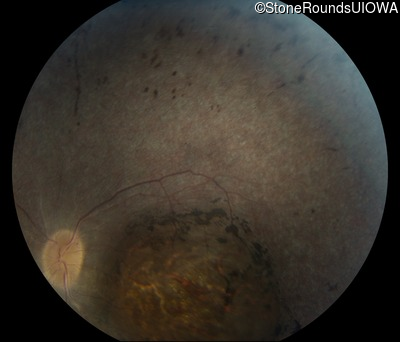

Fundus Photography - Left - Light Perception

Exemplar